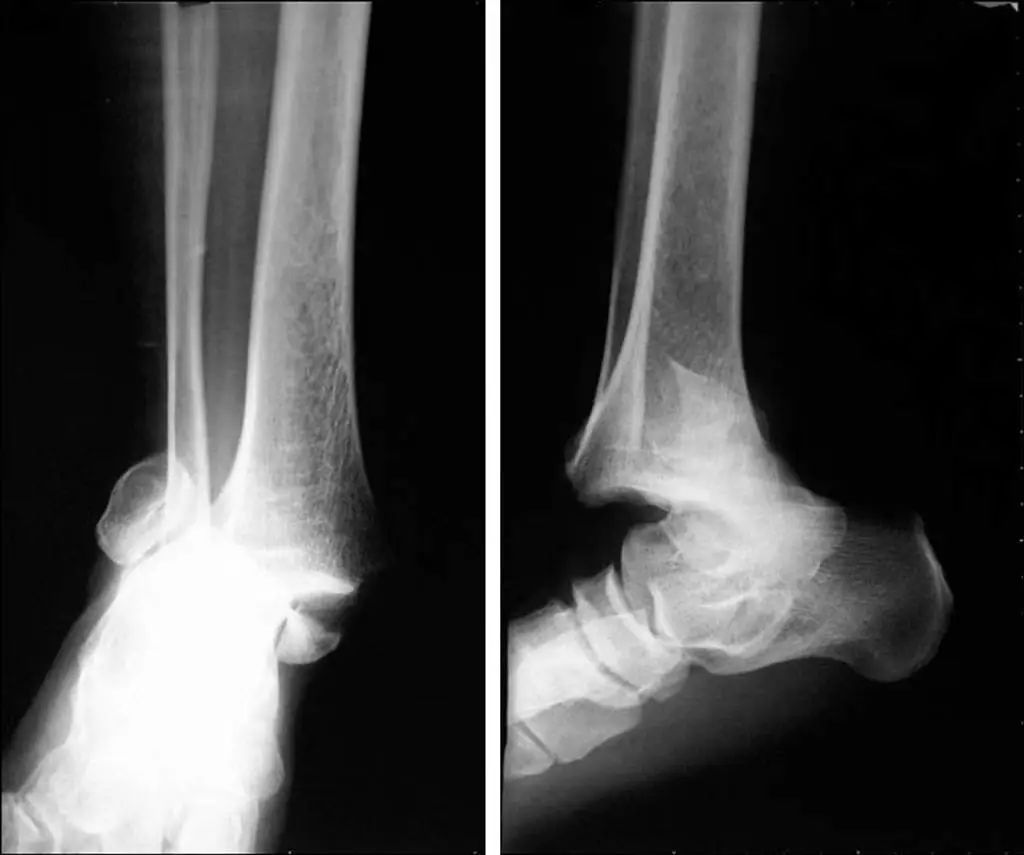

Lorsque l'articulation de la cheville est gravement blessée, la cheville interne et externe et le talus seront déplacés à 11 degrés différents (Figure 11).Les radiographies statiques ne reflètent pas avec précision la stabilité de l'articulation de la cheville.Les radiographies de stress et l'IRM peuvent améliorer l'évaluation de la stabilité de l'articulation de la cheville et des lésions ligamentaires (Figure 12).

Figure 11 Déplacement de la fracture apparemment combiné à une luxation